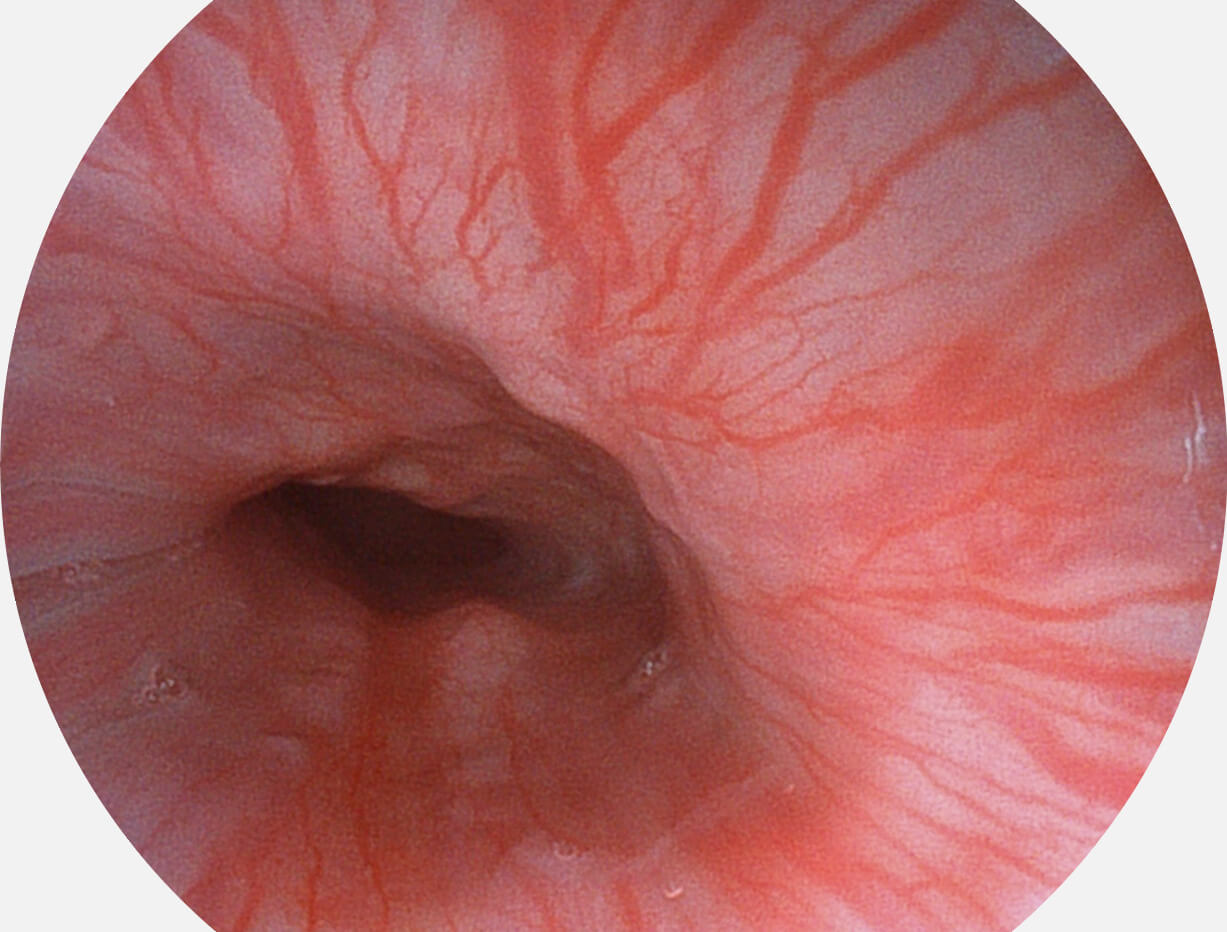

強(qiáng)調(diào)淺層黏膜結(jié)構(gòu)的同時(shí),保證照明亮度和提升淺層微血管與中層血管顏色對比度,病變邊界更清晰。

• 白光圖像 VIST圖像